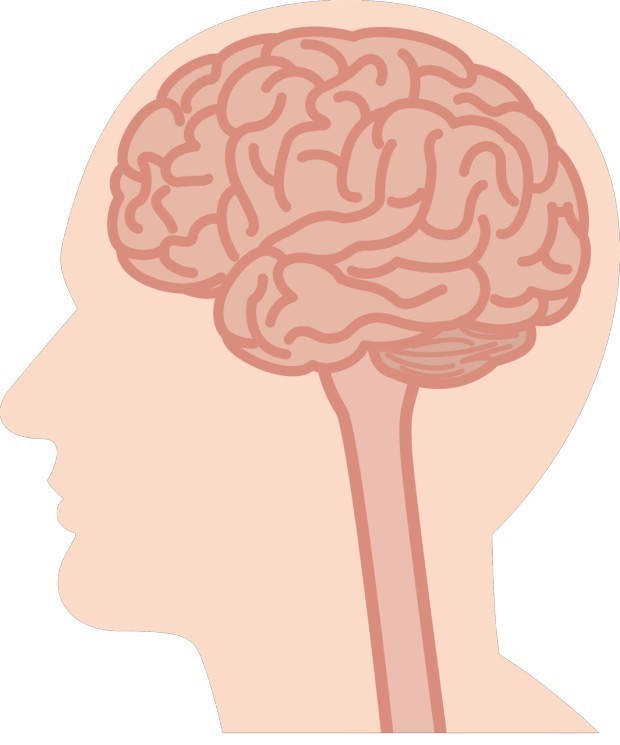

안녕하세요! 오늘은 꼭 알아야 할 생명의 신호, 뇌졸중 전조증상에 대해 알려드립니다 갑작스럽게 찾아오는 뇌졸중(중풍), 그 발생 순간은 예고 없이 오지만, 사실 우리 몸은 미리 신호를 보내고 있습니다. 이 신호를 정확히 알고 빠르게 대응하면 후유증을 줄이고 생명을 구할 수도 있어요. 오늘은 뇌졸중 전조증상 10가지를 아주 상세하게 알려드릴게요. 자신과 가족의 건강을 지키는 데 꼭 기억해두세요.

뇌졸중 전조증상 뇌졸중 전조증상